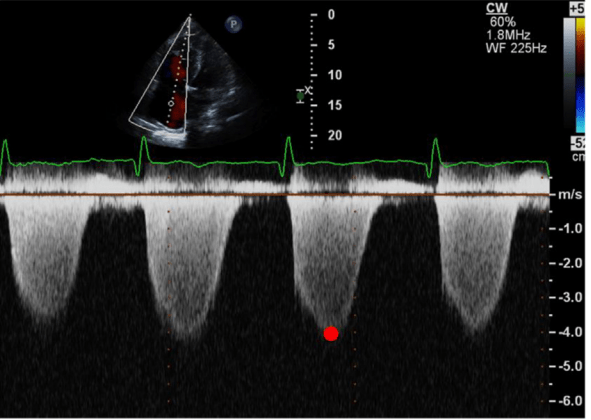

RA 15 mmHg, calculate RVSP, is it high?

RVSP = [4 x (peak TR velocity)2 + RAP]

15 + 64 = 79 mmHg

Cutoff for elevated = <35 normal, 35-49 mild, 50-69 moderate, >70 severe